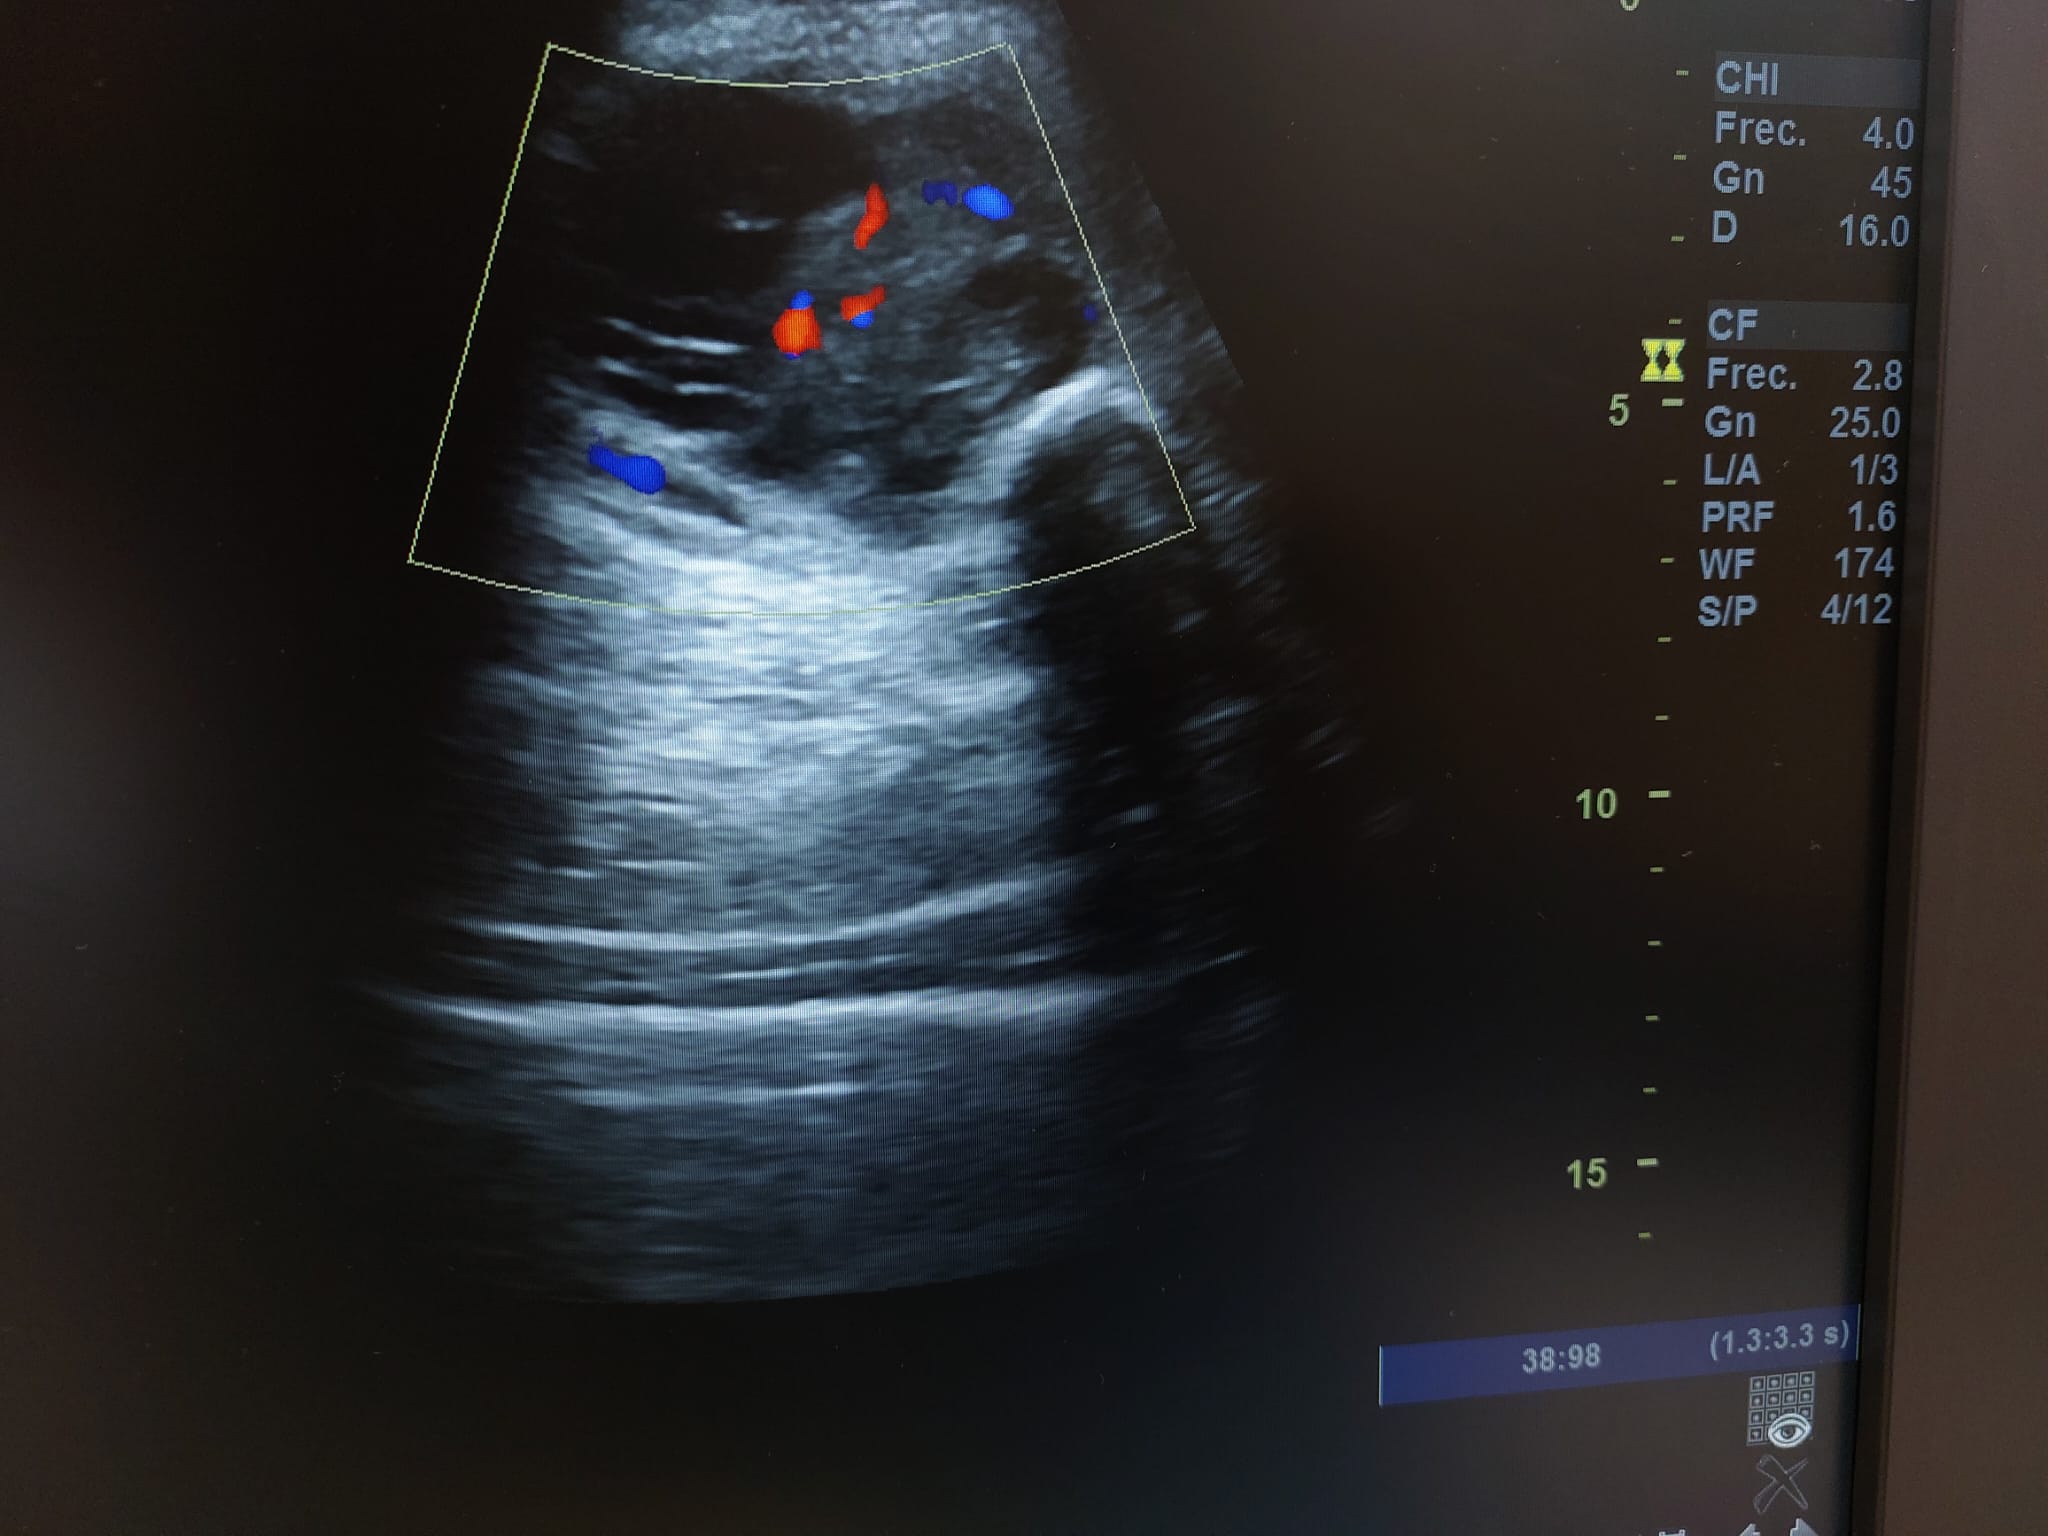

Se realiza ecografía observando colección anecoica a nivel muscular compatible con hematoma organizado, de aproximadamente 7 x 4 cm.

En el seguimiento se observa evolución tórpida sin mejoría clínica y en la ecografía de control se observa aumento notable de tamaño respecto al previo, estructura heterogénea de imagen anecoica con septos internos. Se aprecia edema intramuscular perilesional y captación al activar el Doppler. Se plantea la posibilidad de un hematoma sobreinfectado o, debido a su importante crecimiento, una probable etiología neoplásica. Tras hallazgos descritos en consulta, COT solicita de forma urgente la realización de RNM y biopsia de la lesión. Posteriormente, el resultado de las pruebas complementarias confirman diagnóstico de sarcoma histiocítico.